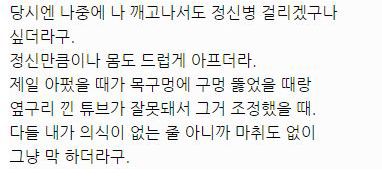

대단한 얘기는 아니지만 중환자실에 3주동안 무의식으로 있었던 썰 풀어볼게